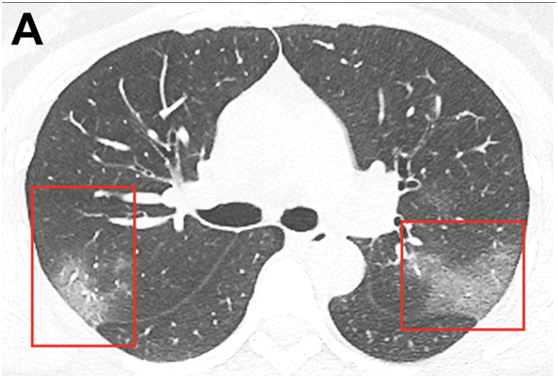

目前,放射科医师们正在努力寻找该病毒在医学影像中的表现。1月31日,北美放射学会(RSNA)在其《放射学》杂志上发表了关于冠状病毒(2019-nCoV)的首批影像研究。这是一个来自中国的案例研究,解读了一名33岁新冠肺炎女性患者的计算机断层成像(CT)。

图A:该患者入院时,未增强的胸部CT显示双侧肺内有多处毛玻璃样混浊。右上叶后段及左上叶顶端后段可见毛玻璃样阴影。

研究指出,影像学检查是2019-nCoV诊断的关键组成部分。双侧对称的肺周混浊是2019新型冠状病毒肺炎的常见CT表现。早期疾病识别不仅对及时治疗至关重要,而且对患者隔离和有效的公共卫生控制和应对也至关重要。